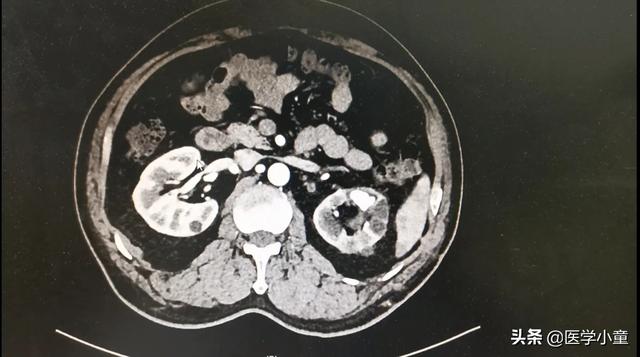

4.結石除去のための経皮的腎結石破砕術超音波またはX線による局在診断のもと、腰背部から穎果または腎盂に直接細い針を刺して拡張し、皮膚から腎臓への通路を作り、腎鏡下で結石を除去または破砕する。小さな結石は腎鏡を通して結石把持器で除去し、大きな結石は砕いて水で洗い流す。

低侵襲の経皮的腎結石摘出術を選択すれば、腰部に小さな穴(大豆大)を開けるだけで、腎臓の中に腎臓鏡を通して入り、ドイツのホルミウムレーザーを併用して結石を破砕してから摘出することができる。

注意:経皮的腎結石摘出術のポイントは、患者の腎臓に穴を開けることにあり、慎重に行わないと腎血管を損傷し、出血などの危険な事象を引き起こす可能性があるため、専門医への要求も非常に高い。